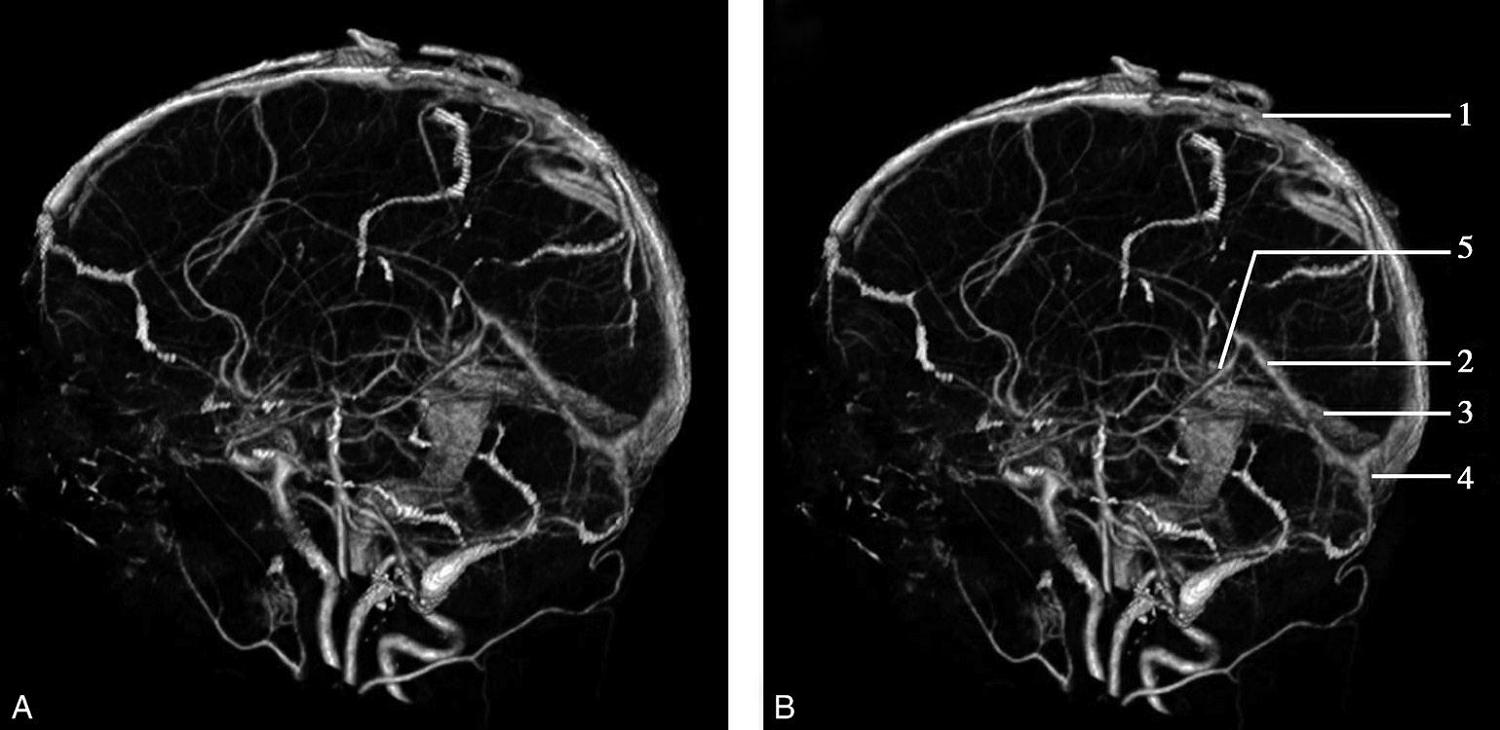

CT血管成像(CT angiography,CTA及CT venography,CTV)通过三维重建技术可显示颅内动静脉的走行、血管壁及血管周围等情况(图1-2-73~图1-2-75)。

图1-2-75 正常颅脑CTV

A.侧位;B.侧位标注

1.上矢状窦;2.直窦;3.乙状窦;4.窦汇;5.大脑大静脉